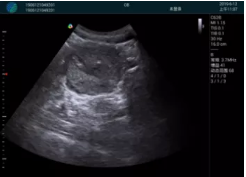

甲狀腺囊性結(jié)節(jié),囊壁鈣化,透聲好

甲狀腺囊性占位

2001年美國(guó)健康護(hù)理研究和質(zhì)量監(jiān)督局(AHRQ)批準(zhǔn)了一項(xiàng)關(guān)于提高患者安全性的報(bào)告,建議:在頸內(nèi)靜脈中心置管術(shù)時(shí)使用超聲引導(dǎo)。此后超聲引導(dǎo)穿刺被用于幾乎所有的急診穿刺操作,尤其是血管穿刺。

便攜超聲在急診穿刺中的應(yīng)用: